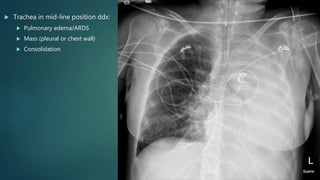

 Trachea in mid-line position ddx:

 Pulmonary edema/ARDS

 Mass (pleural or chest wall)

 Consolidation

 Trachea inmid-line position ddx:  Pulmonary edema/ARDS  Mass (pleural or chest wall)  Consolidation